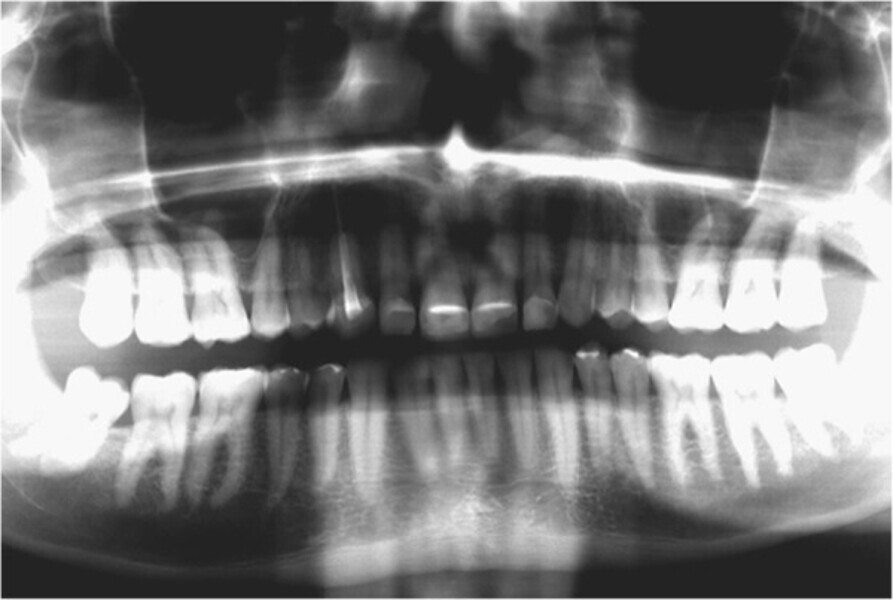

Fig. 2. Situación inicial, radiografía panorámica (2015).